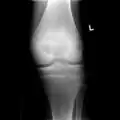

3. X-ray of chondroblastoma of large long bone of lower leg, near the knee